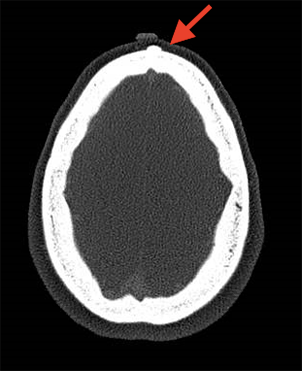

The patient in this case study is a 52 year-old female who has had a forehead growth for many years. More recently she has noted discomfort and increased size of the area. She was also bothered by its appearance and wanted to have it removed. A CT scan, performed before surgery, confirmed the diagnosis of osteoma.

Osteomas affect all ages, including children, but are most commonly diagnosed in patients between the ages of 40 and 60. While osteomas are not cancerous, they can still cause symptoms such as headaches, sinus infections, facial asymmetry, hearing issues, and/or vision problems. The type of symptom present varies according to the osteoma’s location within the head and neck. Treatment is only necessary for osteomas that are visible or causing symptoms. Accurate diagnosis of an osteoma often requires a thorough history, physical examination, and radiographic imaging. The latter is most often accomplished with a CT (or CAT scan).

This test can produce high-resolution images of the inside of your head and neck in order to determine the tumor’s size and placement within the body. Osteomas, that are visibly apparent or associated with any of the aforementioned symptoms, often require surgical excision. This is often a simple, same day ambulatory (outpatient), procedure, with little recovery and downtime. Dr. Tanna can often perform the surgery with a minimally invasive endoscopic surgery technique. Alternatively, larger or more difficult to reach osteomas require an open approach.